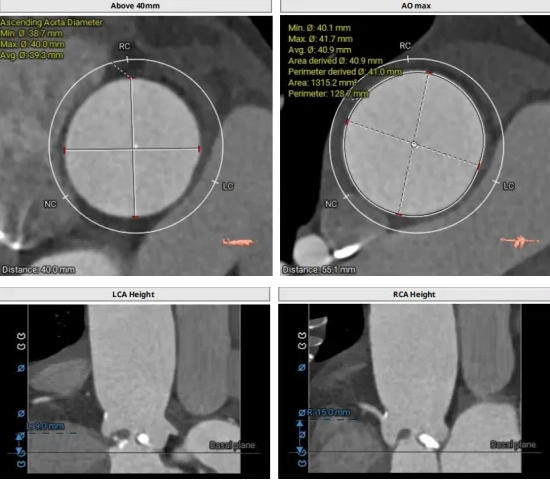

CT結(jié)構(gòu)評(píng)估

患者為功能性二葉瓣,瓣葉增厚,輕度鈣化,鈣化主要集中在左竇瓣葉上,左冠脈高度較低,結(jié)合瓣葉長度,竇部結(jié)構(gòu)綜合評(píng)估左冠風(fēng)險(xiǎn)較低,但左冠瓣葉瓣尖處有鈣化團(tuán)塊,在球擴(kuò)以及瓣膜釋放時(shí)仍需注意左冠灌注情況,由于鈣化團(tuán)塊位置特殊,建議做冠脈保護(hù)處理,右側(cè)股動(dòng)脈作為主入路,穿刺點(diǎn)位于股骨頭中段即可。